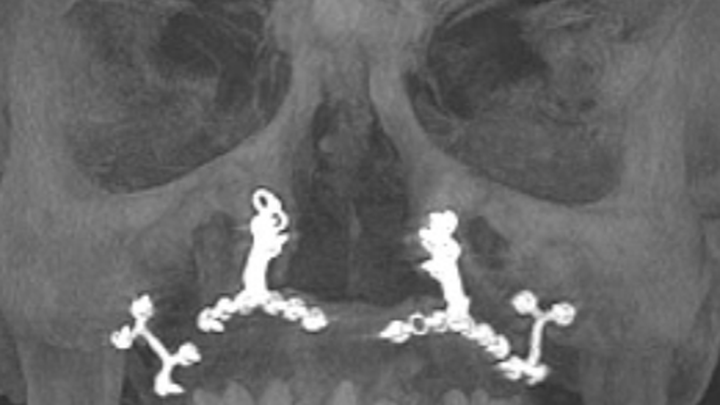

If you're reading this, chances are you know me. My name is Norman Walsh, and I'm reaching out to you for support during a challenging chapter in my life. For those who have knew me 30 years ago, you are likely aware that I survived a devastating car accident that should have claimed my life. I consider myself incredibly fortunate. Thanks to the expertise of skilled surgeons in Boston, I underwent extensive facial reconstructive surgery, which included the insertion of titanium implants to rebuild my jaw, face, and skull. These remarkable procedures, along with the use of one of my ribs to reconstruct my nose, allowed me to reclaim a semblance of normalcy and live a fulfilling life.

However, as time has passed, the effects of the accident have resurfaced. The titanium screws that once held my jaw together have begun to fail. About two years ago, I noticed the screw heads protruding through the roof of my mouth, some eventually fell completely out. Despite the initial success of the surgeries, I now find myself in need of further intervention to address the complications that have arisen. Essentially, the hardware installed 30 years ago has now failed.

Initially, the estimated cost for the necessary surgeries were quoted at $46,000 by the doctor who performed my procedures two years ago. However, I now have found an amazing doctor willing to do it for less,$40,000. This is great news because this doctor is better, and I didn’t really want to go back to the same doctor who installed the currently failing hardware. This new quote includes the full oral surgery needed to restore my health and smile. The surgery will involve the removal of old hardware, multiple bone grafts, a sinus lift, and the insertion of new titanium hardware to hold my jaw together.